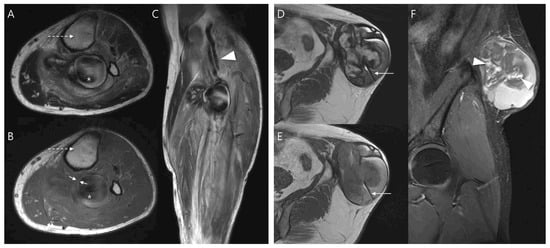

Figure 4.

Diagnosis and treatment of chronic expanding hematoma. (A) Sagittal and axial T2-weighted MR images demonstrate a multilobular, subcutaneous mass (thick arrows) with internal septations. The lesion shows peripheral nodular enhancement (thin arrows, granulation tissue) on coronal T1-weighted contrast-enhanced MR image. (B) Ultrasound-guided biopsy was performed using a core needle (arrows), confirming the hematoma. (C) Gross photograph of the wide excision demonstrates chronic expanding hematoma.